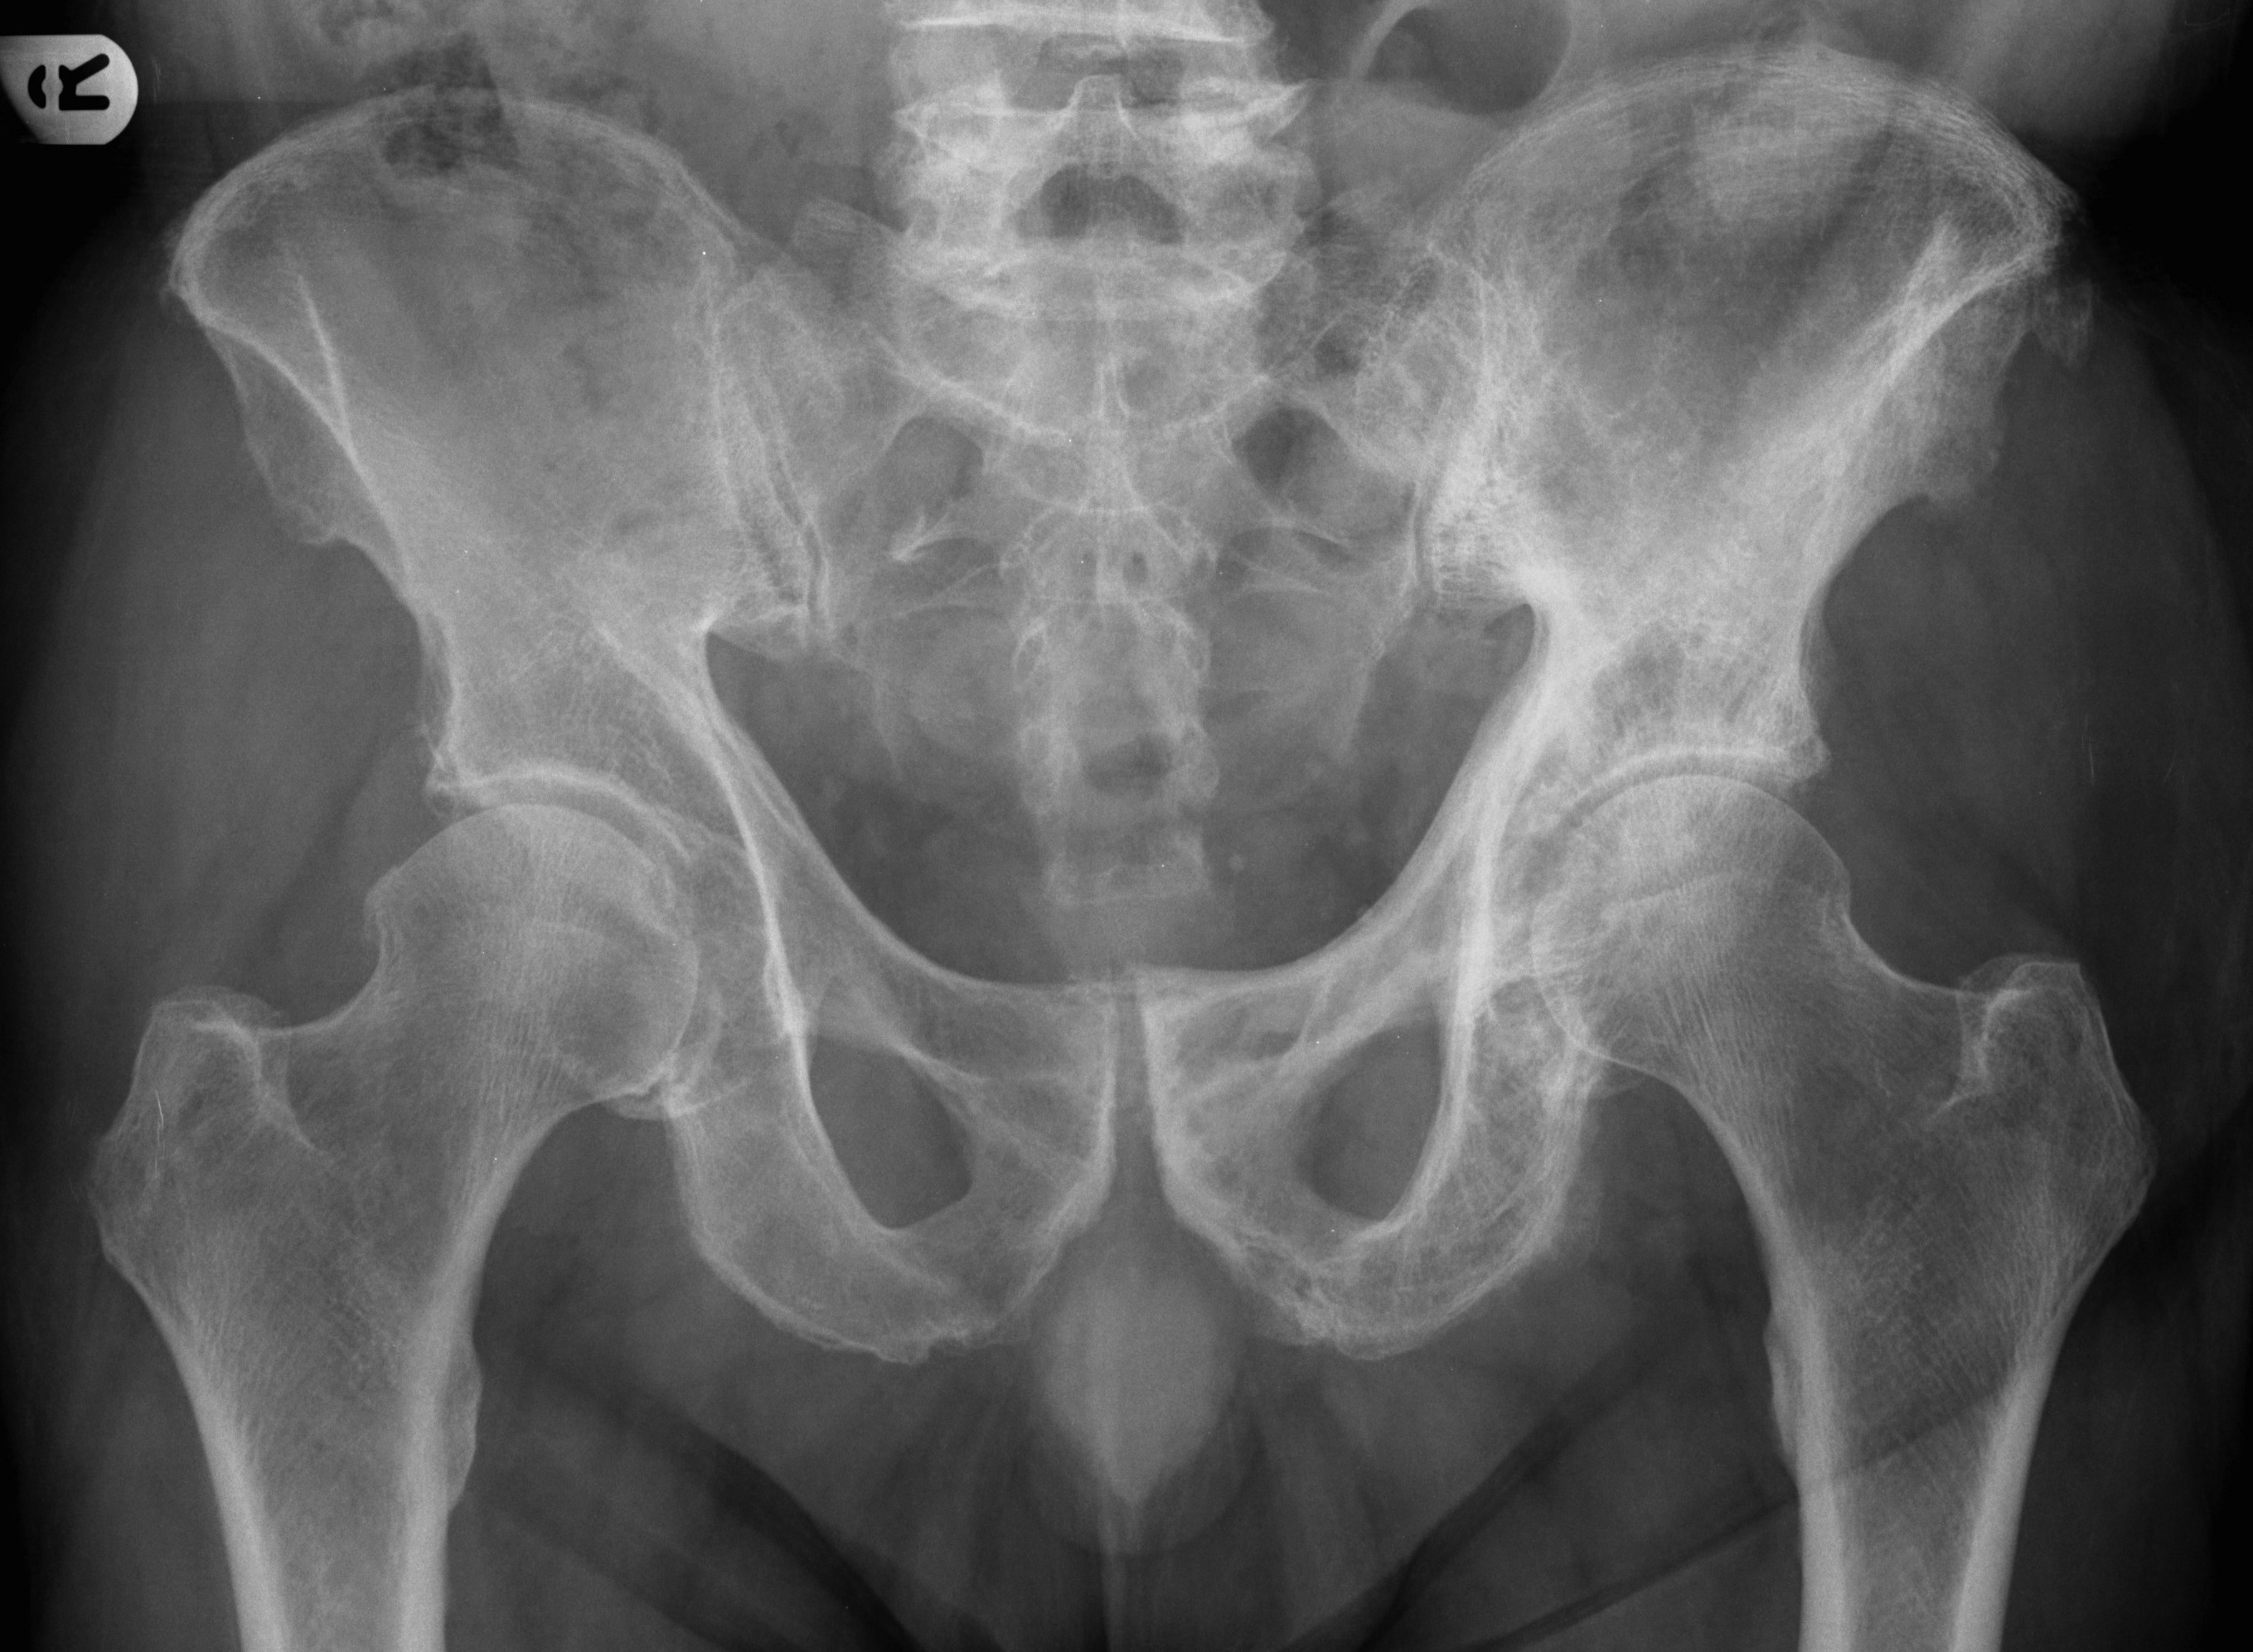

Welche Befunde, passend zu welcher Pathologie zeigt das linke Hemipelvis auf dem vorliegenden Röntgenbild?